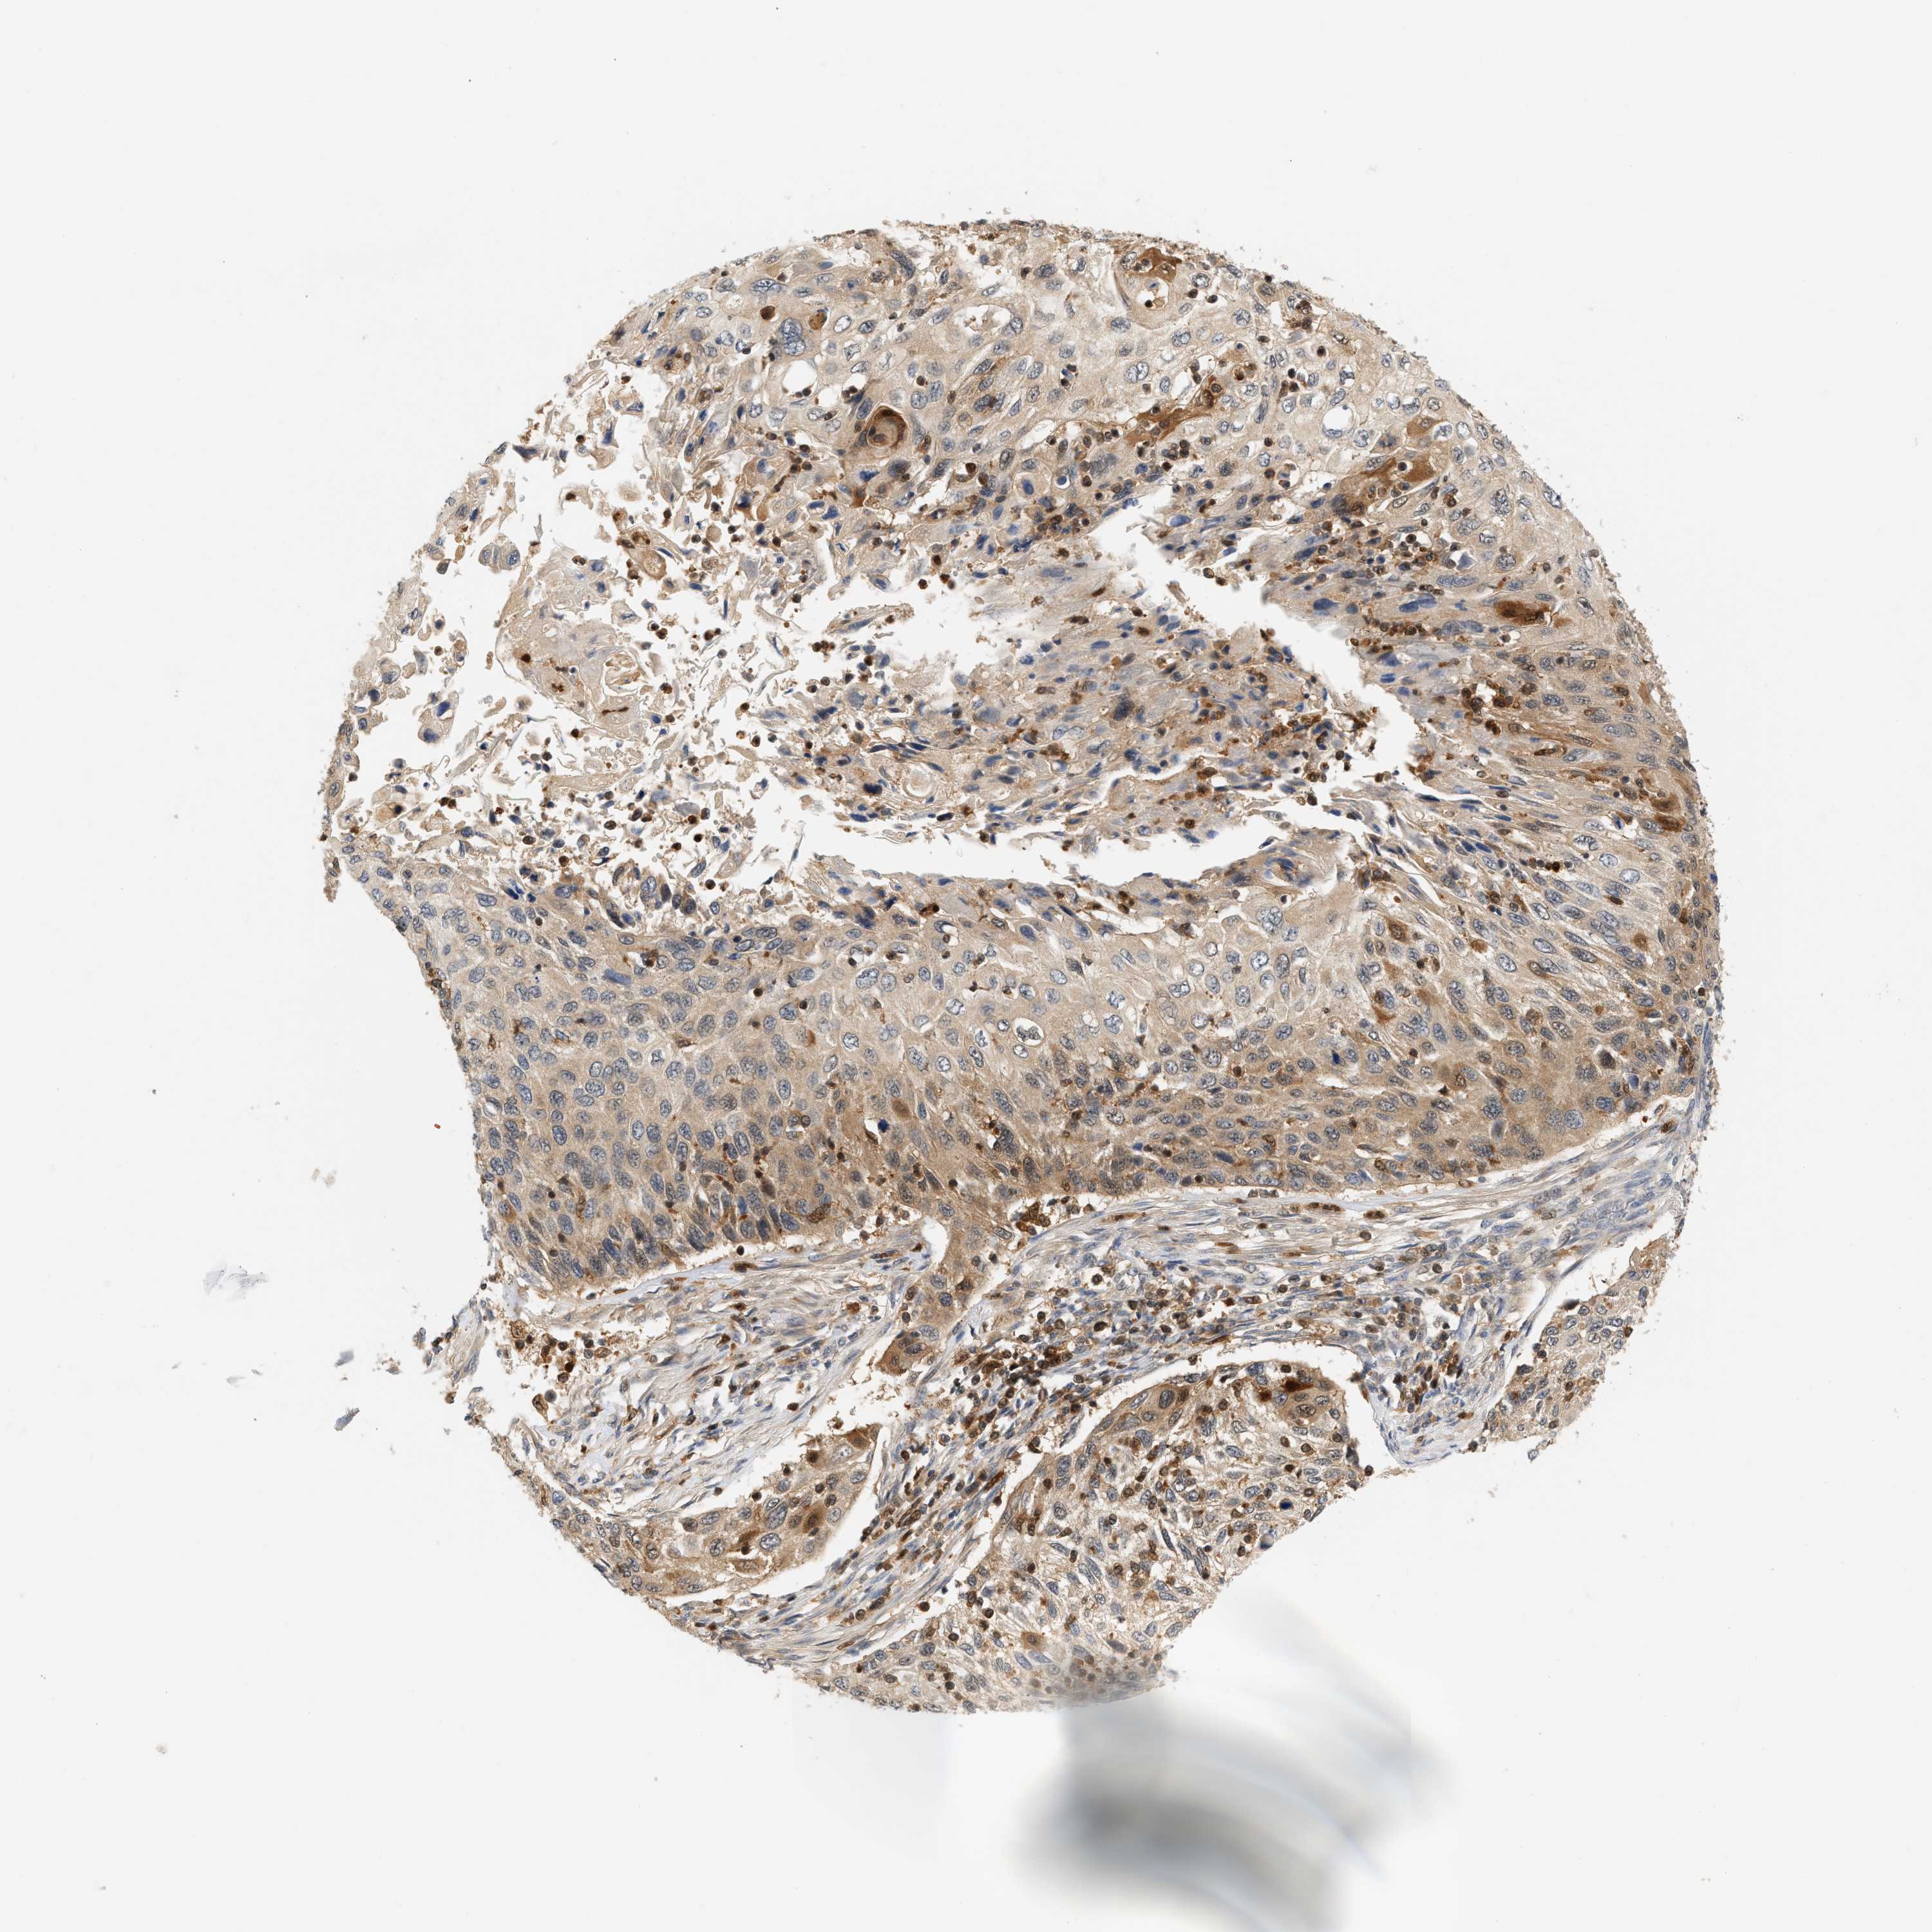

CERVICAL CANCER - Protein expressioni

A mouse-over function shows sample information and annotation data. Click on an image to view it in a full screen mode. Samples can be filtered based on level of antibody staining by selecting one or several of the following categories: high, medium, low and not detected. The assay and annotation is described here.

Note that samples used for immunohistochemistry by the Human Protein Atlas do not correspond to samples in the TCGA dataset.

Antibody stainingi

Antibody staining in the annotated cell types in the current human tissue is reported as not detected, low, medium, or high, based on conventional immunohistochemistry profiling in selected tissues. This score is based on the combination of the staining intensity and fraction of stained cells.

Each image is clickable and will lead to virtual microscopy that enables deeper exploration of all samples and also displays staining intensity scores, fraction scores and subcellular localization as well as patient and tissue information for each sample.

Antibody HPA049074

Antibody HPA054496

Antibody CAB006853

Antibody CAB015948

Staining

High

Medium

Low

Not detected

Intensity

Strong

Moderate

Weak

Negative

Quantity

>75%

75%-25%

<25%

None

Location

Nuclear

Cytoplasmic/membranous

Cytoplasmic/membranous,nuclear

Adenocarcinoma, NOS